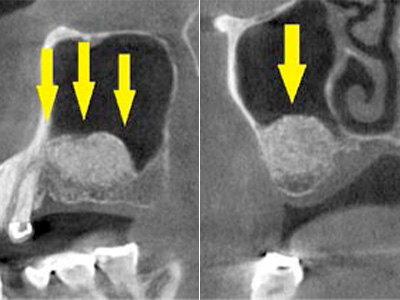

インプラントを埋入するために骨を増やす方法はいくつかありましたが、この場合、患者様ご自身の骨をブロック状で移植するのが最も適していると判断し、自家骨移植術を行ないました。

患者様ご自身の下顎前歯の下方から骨を採取して、骨がなかった部位に移植しスクリューで固定したCT画像です。

黄色矢印部分が、2つの骨片を移植して、固定したところです。 -

手術後の、別な方向からみたCT画像です。

術前に大きく吸収されていた部分に骨のブロックが移植され、骨が造成されています。

真っ白にピンのように写るのは(黄色矢印)、骨を固定した小さなスクリューです。 -